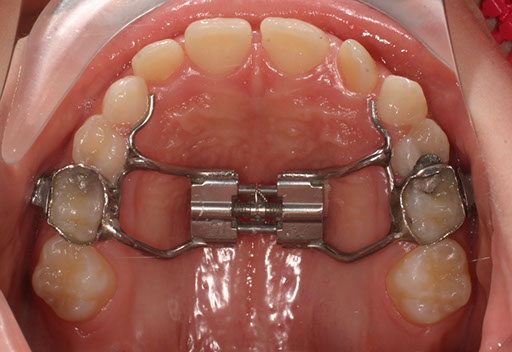

Talvolta, quando si vuole espandere l’arco palatino iposviluppato,  può essere necessario applicare un Diastasatore